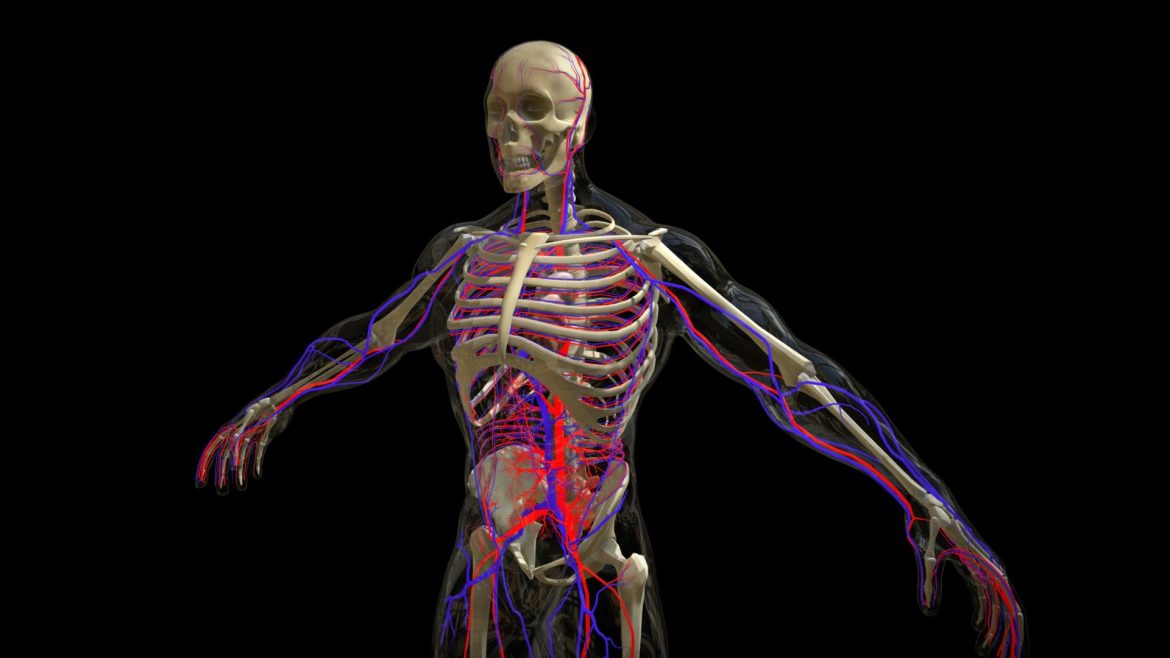

Male Circulatory System with Skeleton. Download includes OBJ, FBX, Maya 2018 (Arnold Render) and 3D Studio Max 2016 (Mental Ray Render). Maya and 3D Studio Max Files have Skin xRay Shaders.

| 3D Model formats | FBX, OBJ, BLENDER, TEXTURES, Materials |

| 3D Model details | VR / AR / Low-poly, Textures, Materials, UV Mapping, Scale transformations |

| Triangles | 803k |

| Vertices | 423.5k |

| Category | Characters & Creatures, People |

| Tags | arteries, bones, circulatory, heart, male, man, medical, skeleton, veins |